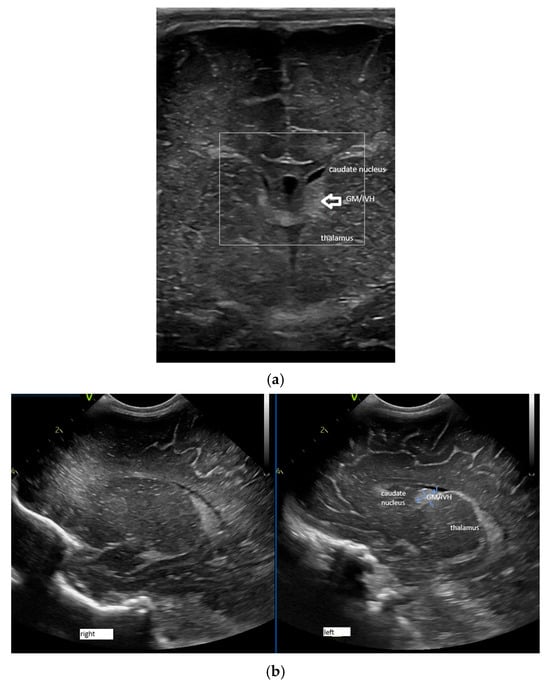

- Confluence posterior to the foramen of Monro, the most frequent variant (Figure 1).

- Confluence at the level of the foramen of Monro (Figure 2).